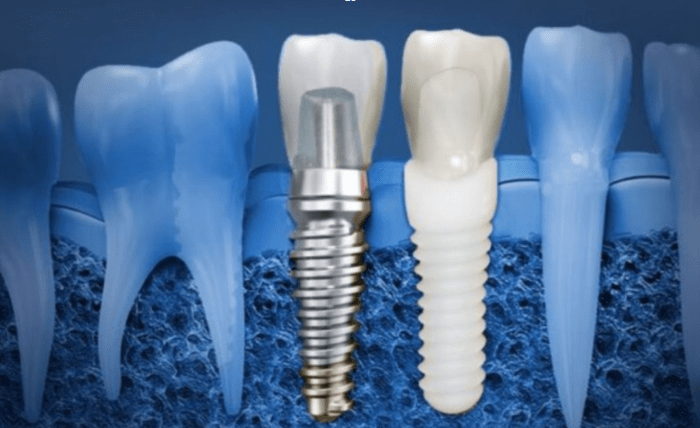

Ceramic implants are becoming a popular choice in dental care. These implants are made from high-quality zirconia, a material that offers a natural-looking and durable solution for replacing missing teeth. Unlike traditional metal implants, ceramic implants provide a more aesthetic option for those seeking a metal-free dental restoration.

Ceramic implants are designed to replace missing teeth with a strong, biocompatible material. Zirconia, the main component, is a white ceramic that blends well with the natural color of your teeth.

This makes it an ideal option for people who want a tooth replacement that looks as close to natural as possible. Ceramic implants are also known for being gentle on the gums, reducing the risk of inflammation or irritation that can sometimes occur with metal implants.